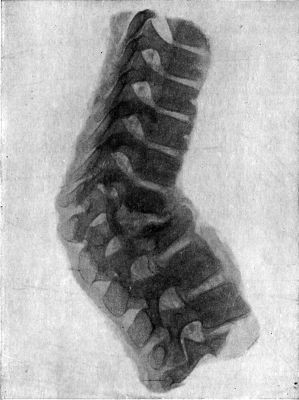

426 208.Fracture-Dislocation of Ninth Thoracic Vertebra

434 212.Radiogram of Museum Specimen of Pott's Disease in a Child

435 213.Radiogram of Child's Thorax showing Spindle-shaped Shadow at Site of Pott's Disease of Fourth, Fifth, and Sixth Thoracic Vertebræ